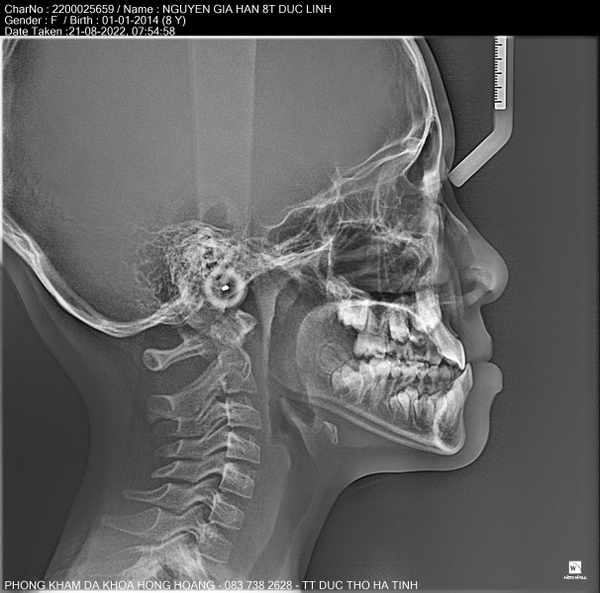

𝐇𝐈̀𝐍𝐇 𝐀̉𝐍𝐇 𝐂𝐇𝐔̣𝐏 𝐏𝐀𝐍𝐎𝐑𝐀𝐌𝐀 (𝐑𝐀̆𝐍𝐆 𝐓𝐎𝐀̀𝐍 𝐂𝐀̉𝐍𝐇) 𝐕𝐀̀ 𝐂𝐄𝐏𝐇𝐀𝐋𝐎 𝐁𝐀̆̀𝐍𝐆 𝐌𝐀́𝐘 𝐂𝐇𝐔̣𝐏 𝐂𝐀̆́𝐓 𝐋𝐎̛́𝐏 𝐕𝐈 𝐓𝐈́𝐍𝐇 𝐑𝐀̆𝐍𝐆 𝐇𝐀̀𝐌 𝐌𝐀̣̆𝐓.

🍀Hình ảnh chụp phim panorama và cephalo (mặt thẳng, mặt nghiêng) giúp bác sỹ răng hàm mặt đánh giá phân tích được khung hàm trên của bệnh nhân và lập kế hoạch điều trị chuẩn xác.

- Mặt nghiêng (lateral cephalometric) : giúp chân đoán hướng tăng trưởng, kiểu mặt, hạng xương, tương quan, hướng tăng trưởng và hình dạng xương hàm dưới, chiều dài nền.